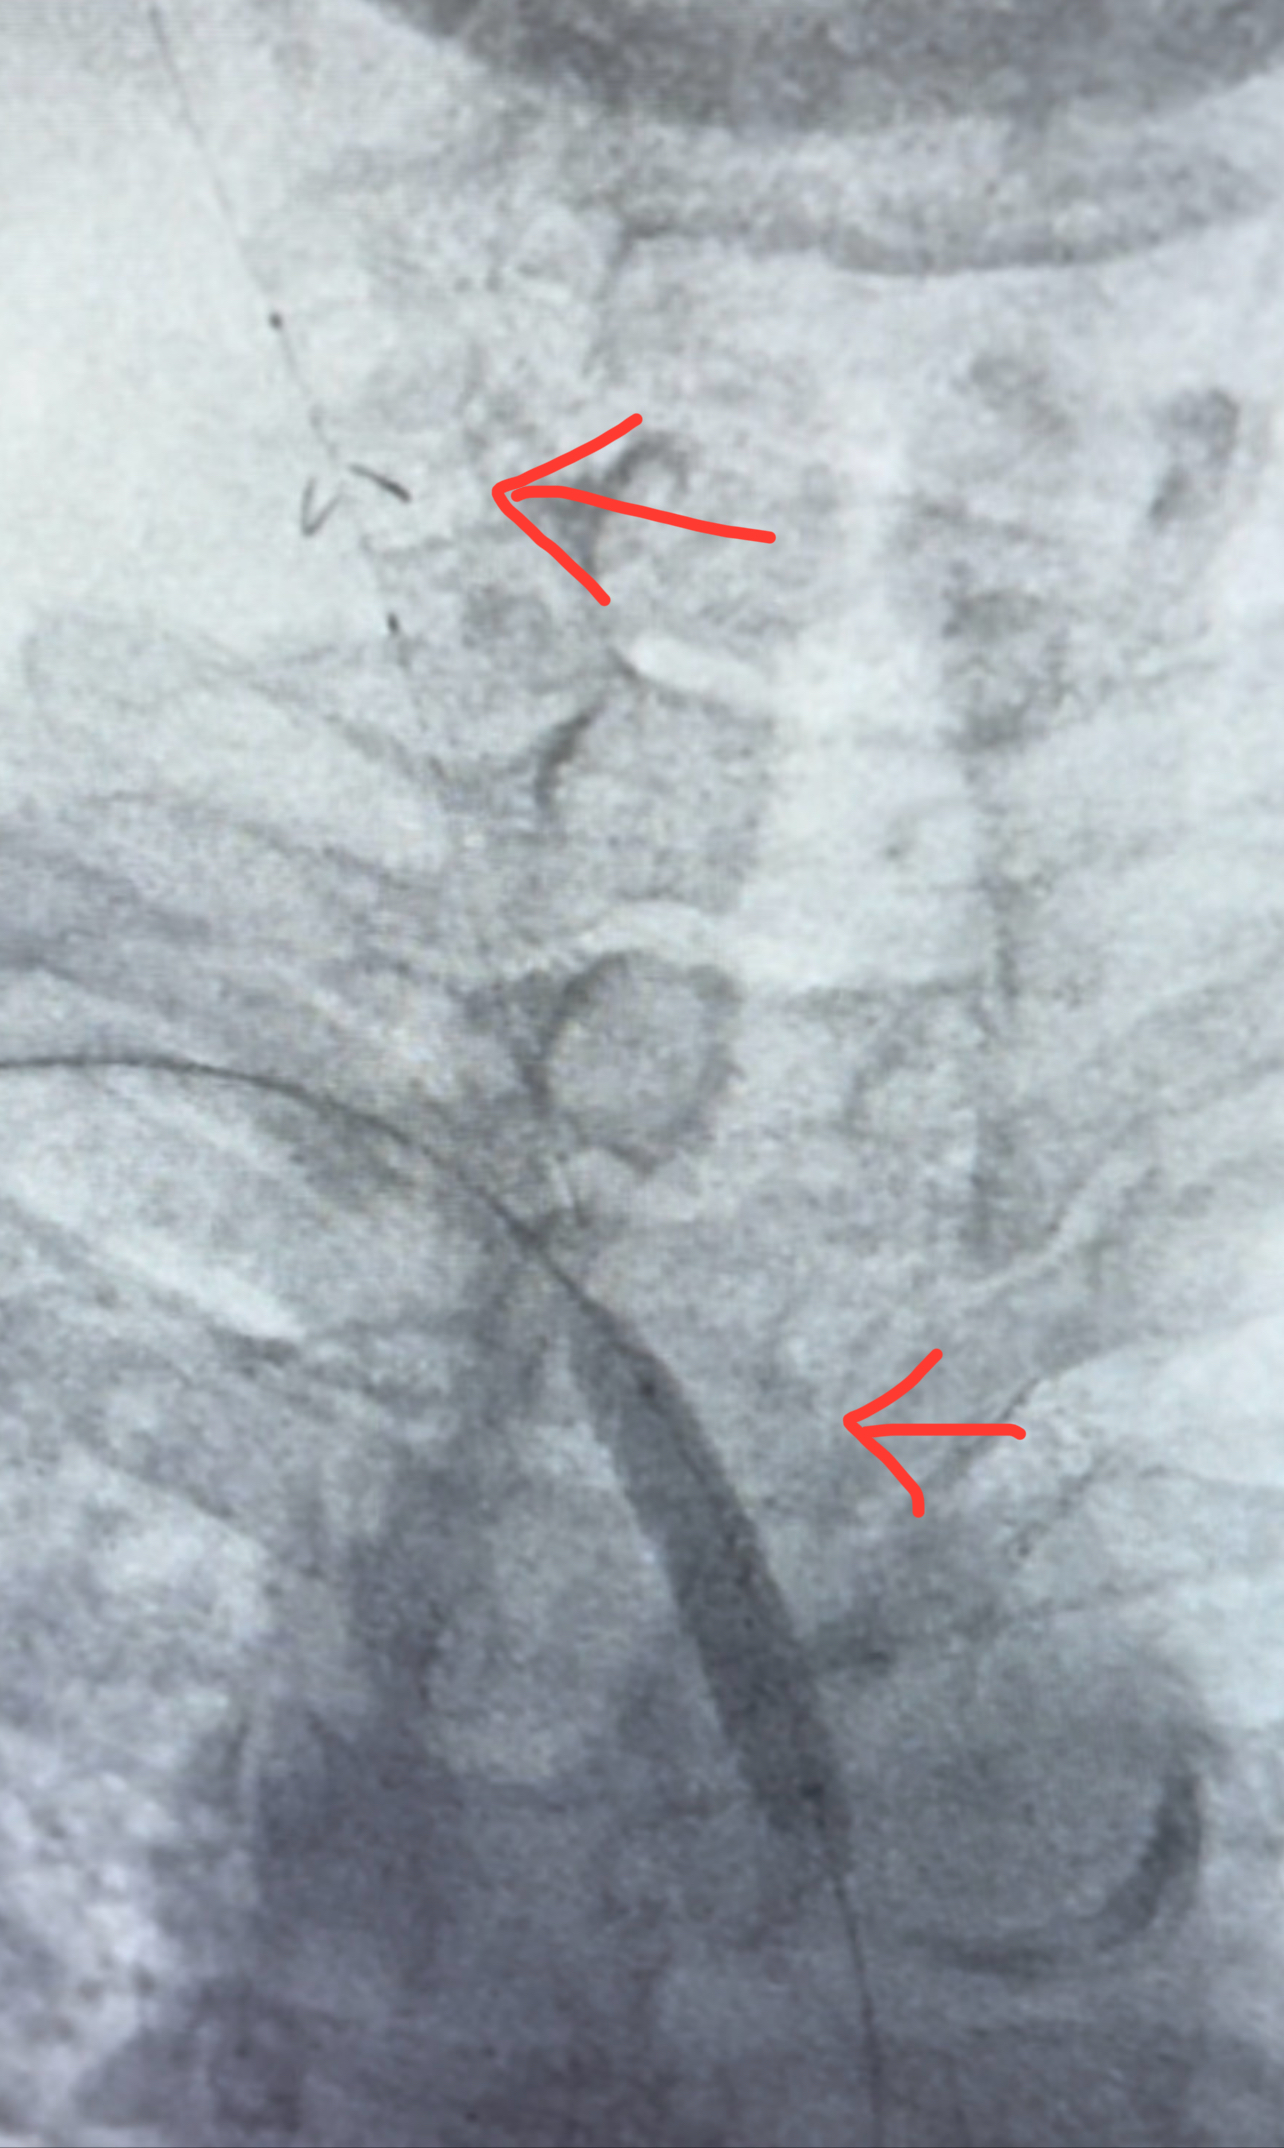

A 70-year-old female with a history of peripheral vascular disease presented with claudication in both arms, manifested as pain in both arms. Her left subclavian was stented months prior to presentation. An aortogram revealed severe stenosis of the innominate artery (Figure 1). Since multiple attempts to cross the lesion antegrade from the femoral access site were unsuccessful, we proceeded with the successful deployment of an embolic protection filter in the right internal carotid artery via our right radial artery access site (Figure 2). Using the right radial artery, we passed a long run-through guidewire into the distal abdominal aorta. Due to severe aortic tortuosity, we were unable to snare the wire from the aorta. Therefore, we upsized the radial sheath to 7 French over both wires (runthrough and bare). Using a support catheter, we exchanged the runthrough wire for a Glidewire Advantage. We advanced an 8 x 29mm balloon expandable stent to the area of innominate stenosis and deployed it (Figure 3). We postdilated the stent with a 14mm balloon. Angiography demonstrated adequate expansion. On follow up, the patient was without claudication and had triphasic flow in the innominate and left subclavian arteries.